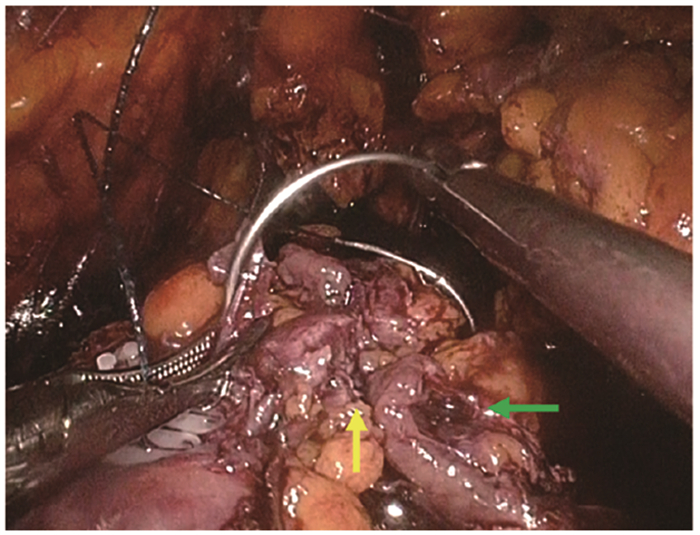

结果   14例AML患者中有1例相对孤立肾合并AML、7例多发AML、8例巨大AML(肿瘤最大直径>7 cm)、6例紧邻肾集合系统或肾门的AML以及2例合并出血破裂史AML, 病情复杂, 手术难度大。采取经腹腔镜或开放肾部分切除或肿瘤剜除术后, 顺利切除肿瘤, 病理检查提示肾AML, 术后定期门诊随访, 行CT扫描均无复发。全部患者术后肾功能保持良好, 术前和术后1个月血肌酐水平分别为(84.1±26.8)μg/ml和(97.5±37.0)μg/ml, 两组数据差异无统计学意义(t=-3.193, P>0.05)。

Results  Among 14 patients with renal AML, 1 had a relative solitary kidney with AML, 7 had multiple AML, 8 had huge AML (the maximum diameter of the tumor >7 cm), 6 had AML adjacent to the renal collection system or the renal portal, and 2 had AML combined with bleeding and rupture history; all cases were complicated and difficult to treat. All operations were successfully performed by laparoscopic or open partial nephrectomy or enucleation of the tumor, and pathological examination indicated renal AML. All patients were regularly followed up and no recurrence was found by CT scanning. The renal function of all patients was well preserved; the concentration of serum creatinine before and 1 month after the operation were (84.1±26.8)μg/ml and (97.5±37.0)μg/ml respectively, without statistically insignificant difference (t=-3.193, P>0.05).